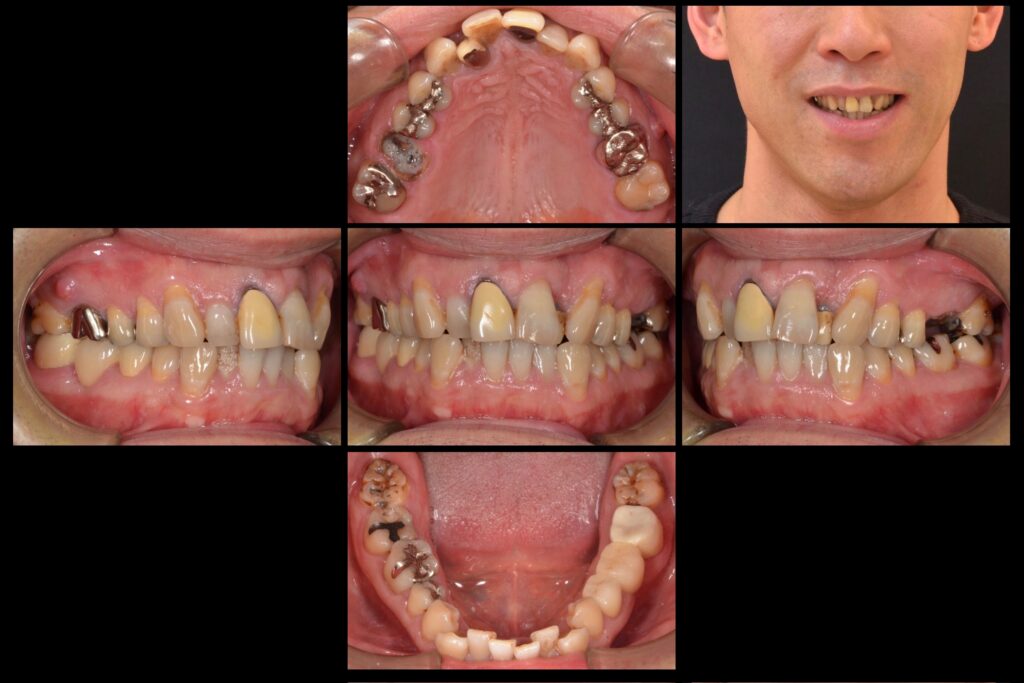

まず、虫歯は治療した箇所の中に出来る2次う蝕でした。特に銀歯は隙間が開きやすく、そこから唾液にのって虫歯菌が侵入し銀歯の下に大きな虫歯を形成します。

また、前歯は凹凸し、内側に引っ込んでる歯もあります。奥歯は本来の顎の大きさより狭くなっており窮屈な状態でした。

| 主訴 | 虫歯と歯並びを治したい |

| 診断名 | 2次う蝕・不正咬合 |

| 年齢 | 40代男性 |

| 治療方法 | セラミック治療・矯正治療 |

| 抜歯部位 | 左上6番残根抜歯 |

| 治療期間 | 一年 |

| 治療費 | 20万円/1本 |

| リスク 副作用 | 治療終了後のメンテナンス不足による歯周病 歯ぎしりや過剰な噛み締めによるセラミックスの破折や歯の根の再治療 |